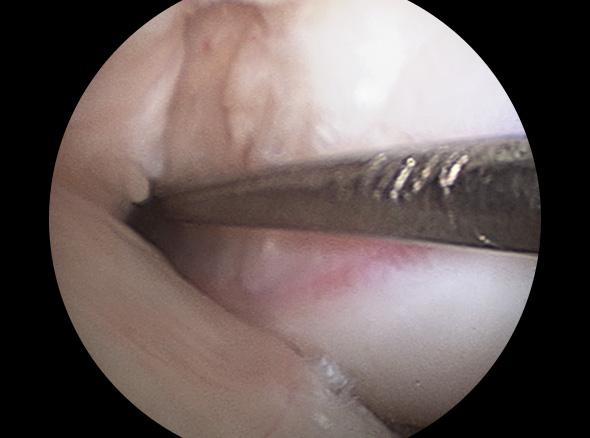

이식할 인대 삽입

이식한 인대 고정